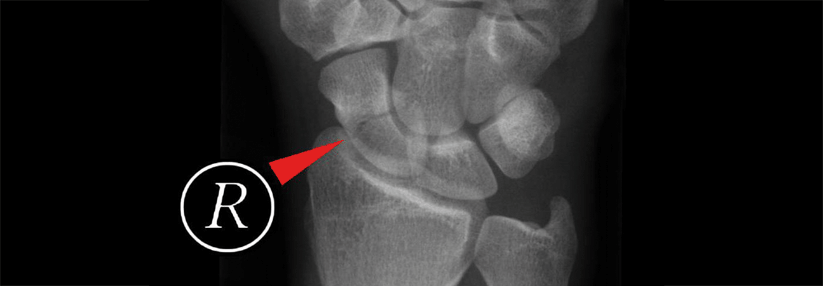

Colles-Fraktur des distalen Radius und Abrissfraktur des Processus styloideus ulnaris­ im Handgelenk einer 94-Jährigen. Colles-Fraktur des distalen Radius und Abrissfraktur des Processus styloideus ulnaris­ im Handgelenk einer 94-Jährigen. © Science Photo Library/Steven Needell